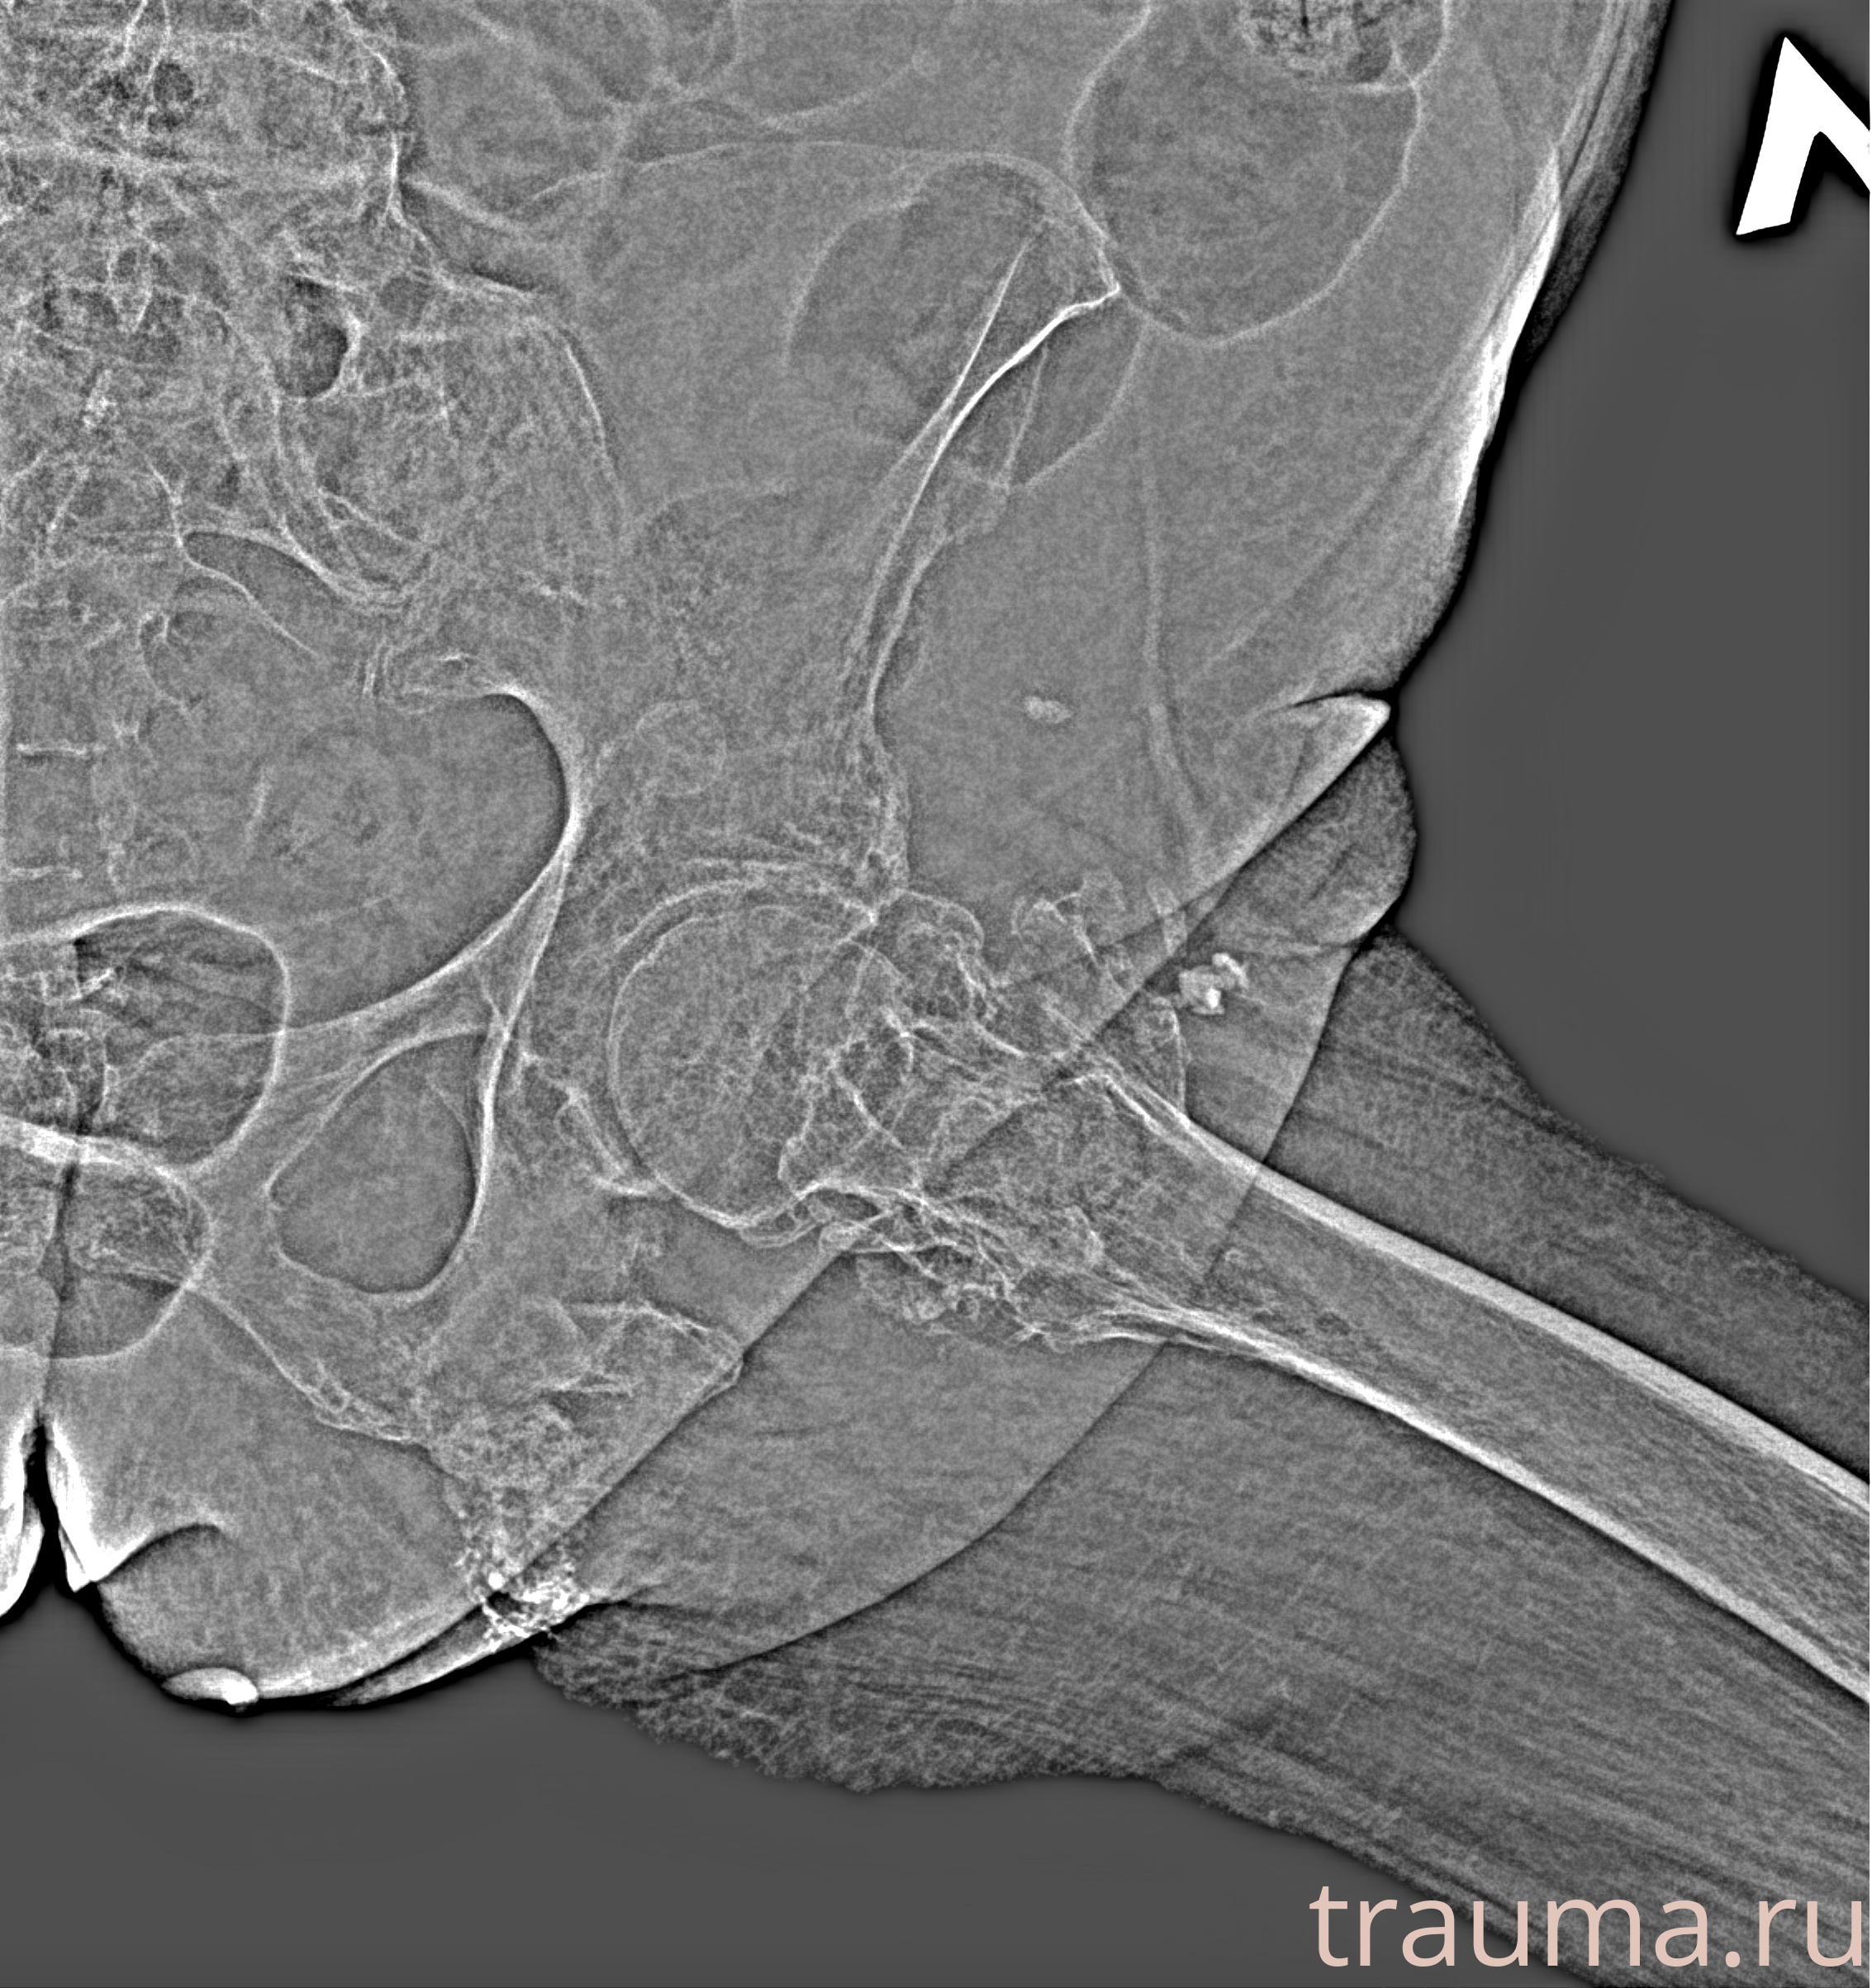

Рентген на дому: по вашему адресу приезжает врач-рентгенолог, травматолог-ортопед с мобильным рентгеновским аппаратом, проводит диагностику травмы или заболевания, делает необходимые рентгенограммы, дает рекомендации по дальнейшему лечению. Получить качественные снимки в домашних условиях возможно благодаря уникальной методике, разработанной МосРентген Центром для института  Склифосовского